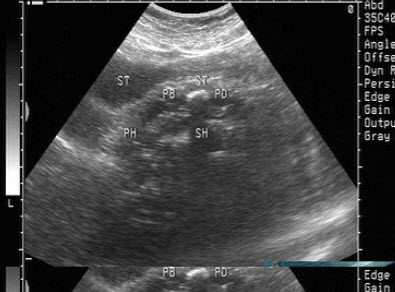

9、单项选择题

患者,急性胰腺炎治疗后,超声见胰管内多个强回声光团,后伴声影,如图所示,考虑为()

A.胰腺胰管结石

B.胰腺脓肿

C.胰腺肿瘤

D.胰腺假性囊肿

E.胰腺胰管钙化